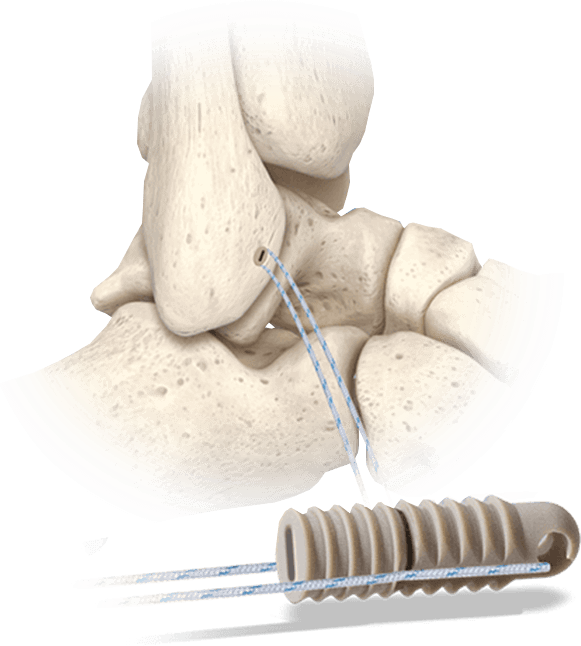

Hercules® Knotless Suture Anchor System

A knotless PEEK anchor system that allows surgeons to implant, tension, and lock the anchor.

Applications:

- Lateral ankle ligament repair (e.g., ATFL)

- Achilles tendon reattachment

- Midfoot and forefoot soft tissue stabilization

Key Advantages:

- Available in 2.5mm, 3.5mm, 4.5mm, and 5.5mm sizes

- Radiolucent PEEK with bone-like modulus

- Knotless design with suture channels for post-insertion tensioning

- Delivered sterile and pre-assembled with a Suture Threader

- Compatible with BightForce™ UHMWPE suture (sold separately)